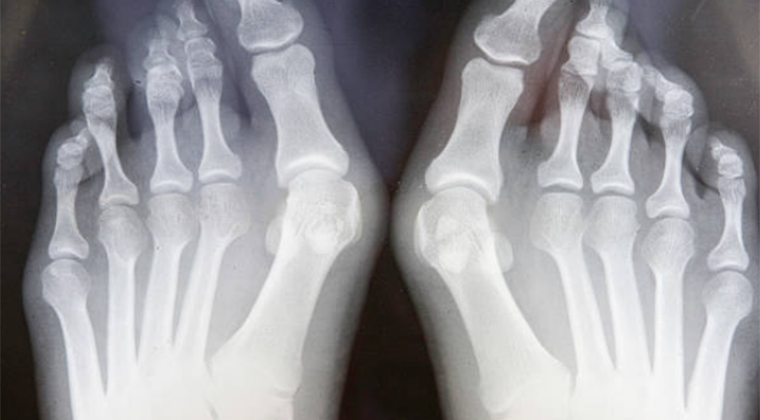

When walking, running, or even standing becomes a painful chore, many turn to surgery, especially for bunions, which can be incredibly debilitating. Traditional bunion surgeries, known as osteotomies, involve cutting the bone and re-aligning the joint. This method, while effective at correcting the deformity, is not without its drawbacks. It often requires significant recovery time and can result in visible scarring and discomfort.